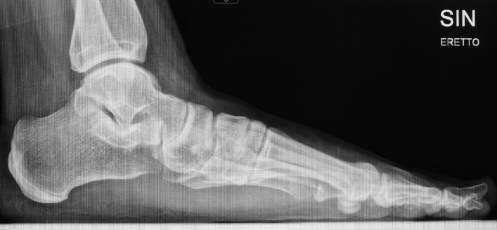

Röntgenbilder

Für die OP-Planung sind auch detaillierte Röntgenbilder unerlässlich. Sie dokumentieren die Fußknochen und den Grad der Fehlstellung aus verschiedenen Blickwinkeln. Am linken Fuß ist die Abweichung des Längsgewölbes und die Verschiebung der Knochen deutlich erkennbar.